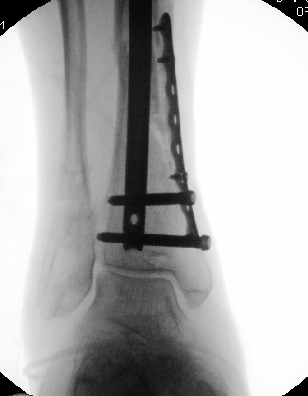

Midshaft #clavicle nonunion prediction at 6 wks post-injury appears superior to time of injury. We found 3 simple clinical predictors can accurately predict #fracture healing in most cases. This months @jbjs / jbjs.org/issue.php from our unit @EdinburghTrauma